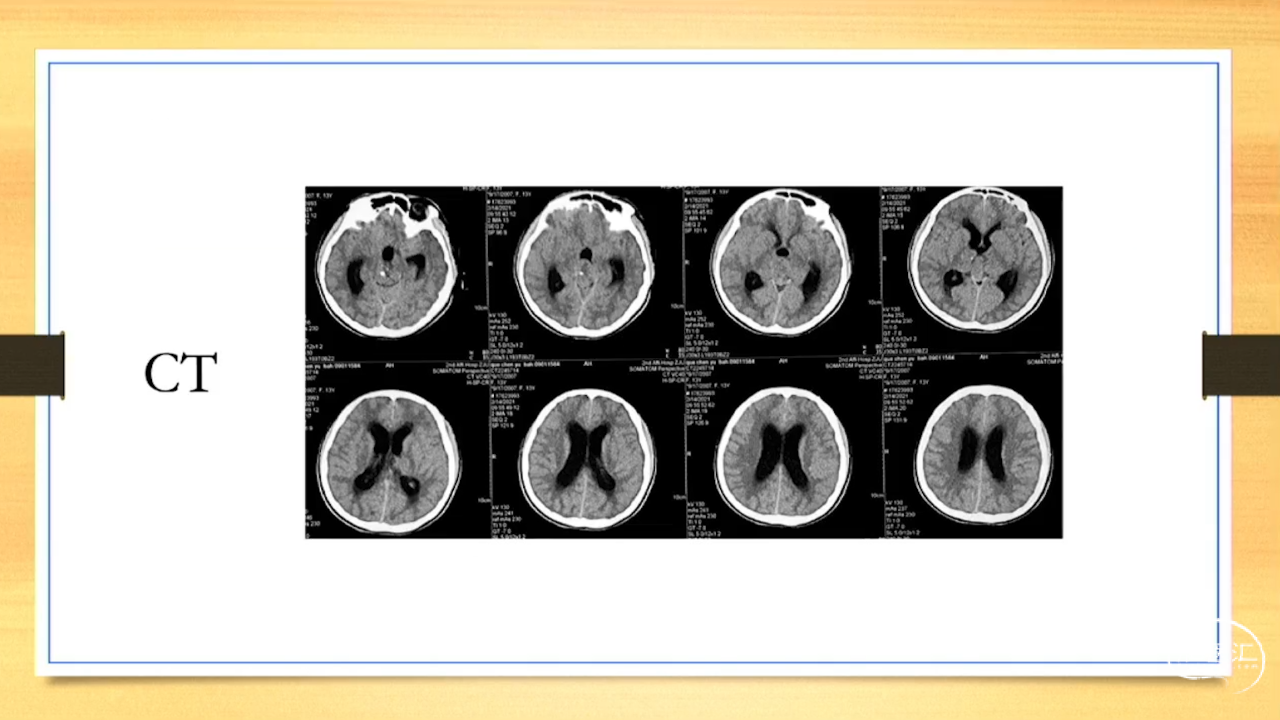

张荣教授:儿童颅内生殖细胞瘤的手术治疗

颅内生殖细胞肿瘤的治疗是手术、放疗、化疗、内分泌及其他多学科的整合治疗。及时、精准、合理的手术治疗是iGCT患者提高生存率、降低并发症、改善神经内分泌功能的关键。